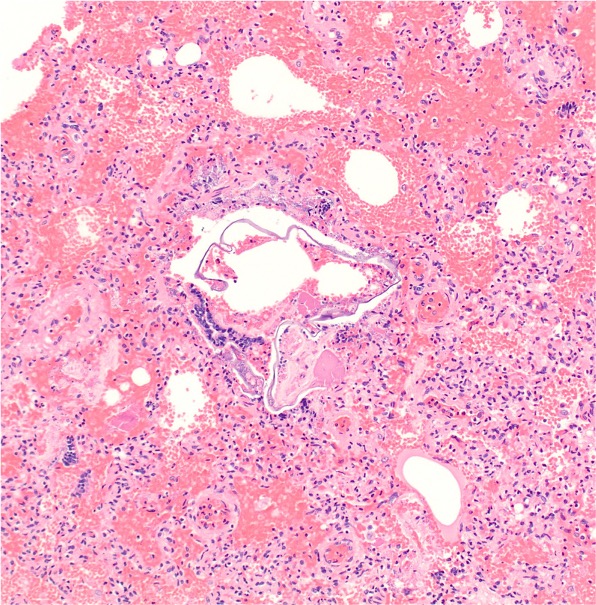

Based on the microscopic images (H&E - 100X), which relevant information has likely been omitted in the case presentation?

A cardiac catheterization procedure was performed with detection of pulmonary arterial hypertension